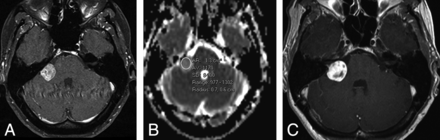

A, Right vestibular schwannoma at baseline on postcontrast axial T1-weighted scan. B, ADC calculation showing minimum value of 977 × 10−6 mm2/s. This would predict treatment failure. C, Four-year follow-up shows tumor growth on the postcontrast axial T1-weighted scan.

A, Postcontrast T1-weighted axial scan through the posterior fossa shows a right cerebellopontine angle vestibular schwannoma. B, The ADC values were calculated from an elliptical region of interest.